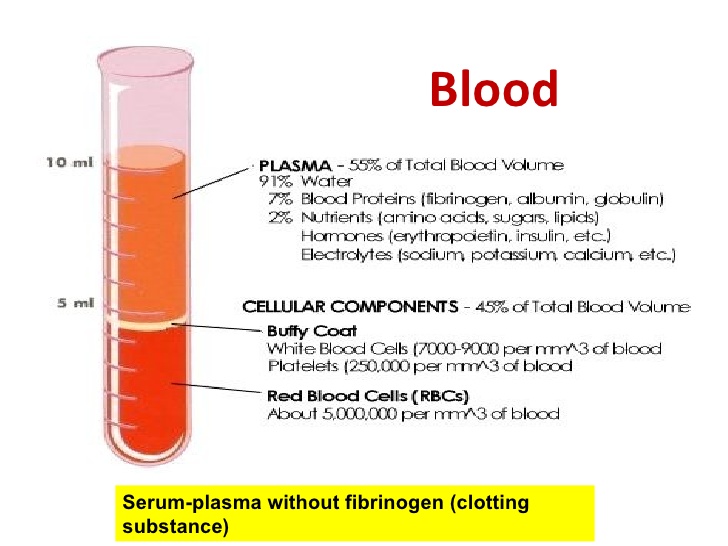

- Components of blood and their functions (Red blood cell, white blood cell, platelets and plasma (blood groups)